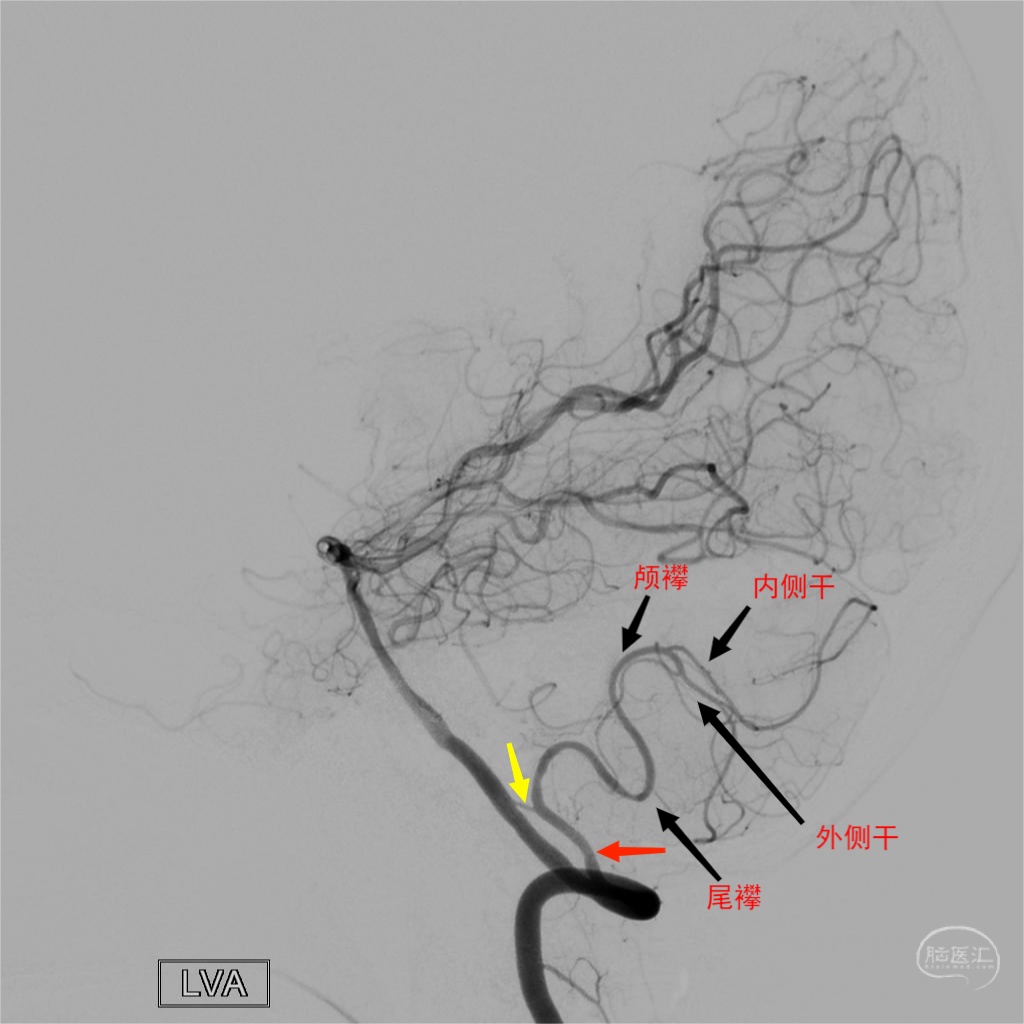

图9 正常小脑后下动脉DSA图像解读。图A为正位,图B为侧位,显示小脑后下动脉尾襻、颅襻、内侧干(蚓部供血)和外侧干(小脑半球枕下面供血)。延髓穿支一般发自于尾襻附近及其近端部位。

图10 小脑后下动脉双干变异。椎基底动脉汇合部动脉瘤(绿箭)合并左侧椎动脉V4段远端狭窄患者,左侧小脑后下动脉呈双干自V4段发出,黄箭所示下干远端主要向蚓部供血,红箭所示上干远端主要向小脑半球枕下面供血,尾襻近端发出延髓穿支(蓝箭)。